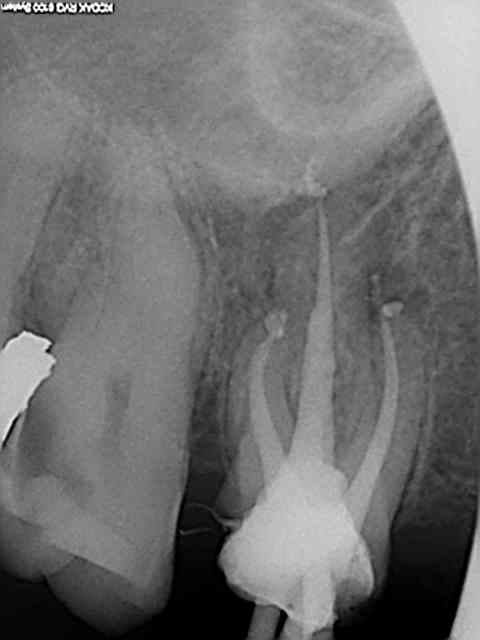

> bref le confrère s'est cassé le Q pour faire des endo corrects

c'est toujours ma première réflexion quand je vois des endos OK et couronnes dévorées bêtement.

Et j'imagine le désarroi du praticien qui a perdu du tempe et peut être de l'argent pour se faire critiquer. Il aurait mieux fait de rien faire et d'envoyer tout de suite chez plumeau (ce que j'aurais fait).

Ce genre d'omnipratique chirphil ? C'est sur c'est rentable mais one shot ! Le patient s'en souvient !

Bon après on refait un autre genre d'omnipratique mais c'est plus long (déposer le bridge l'inlay core ou le sc 33 rte ......)